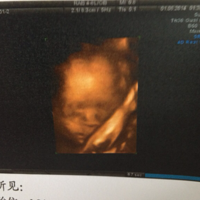

杭州艾玛妇产医院 胎儿排畸关键一步 4D彩超团购火爆开始Ing~

39981004 2015-04-01 11:24

2989 浏览 查看原帖